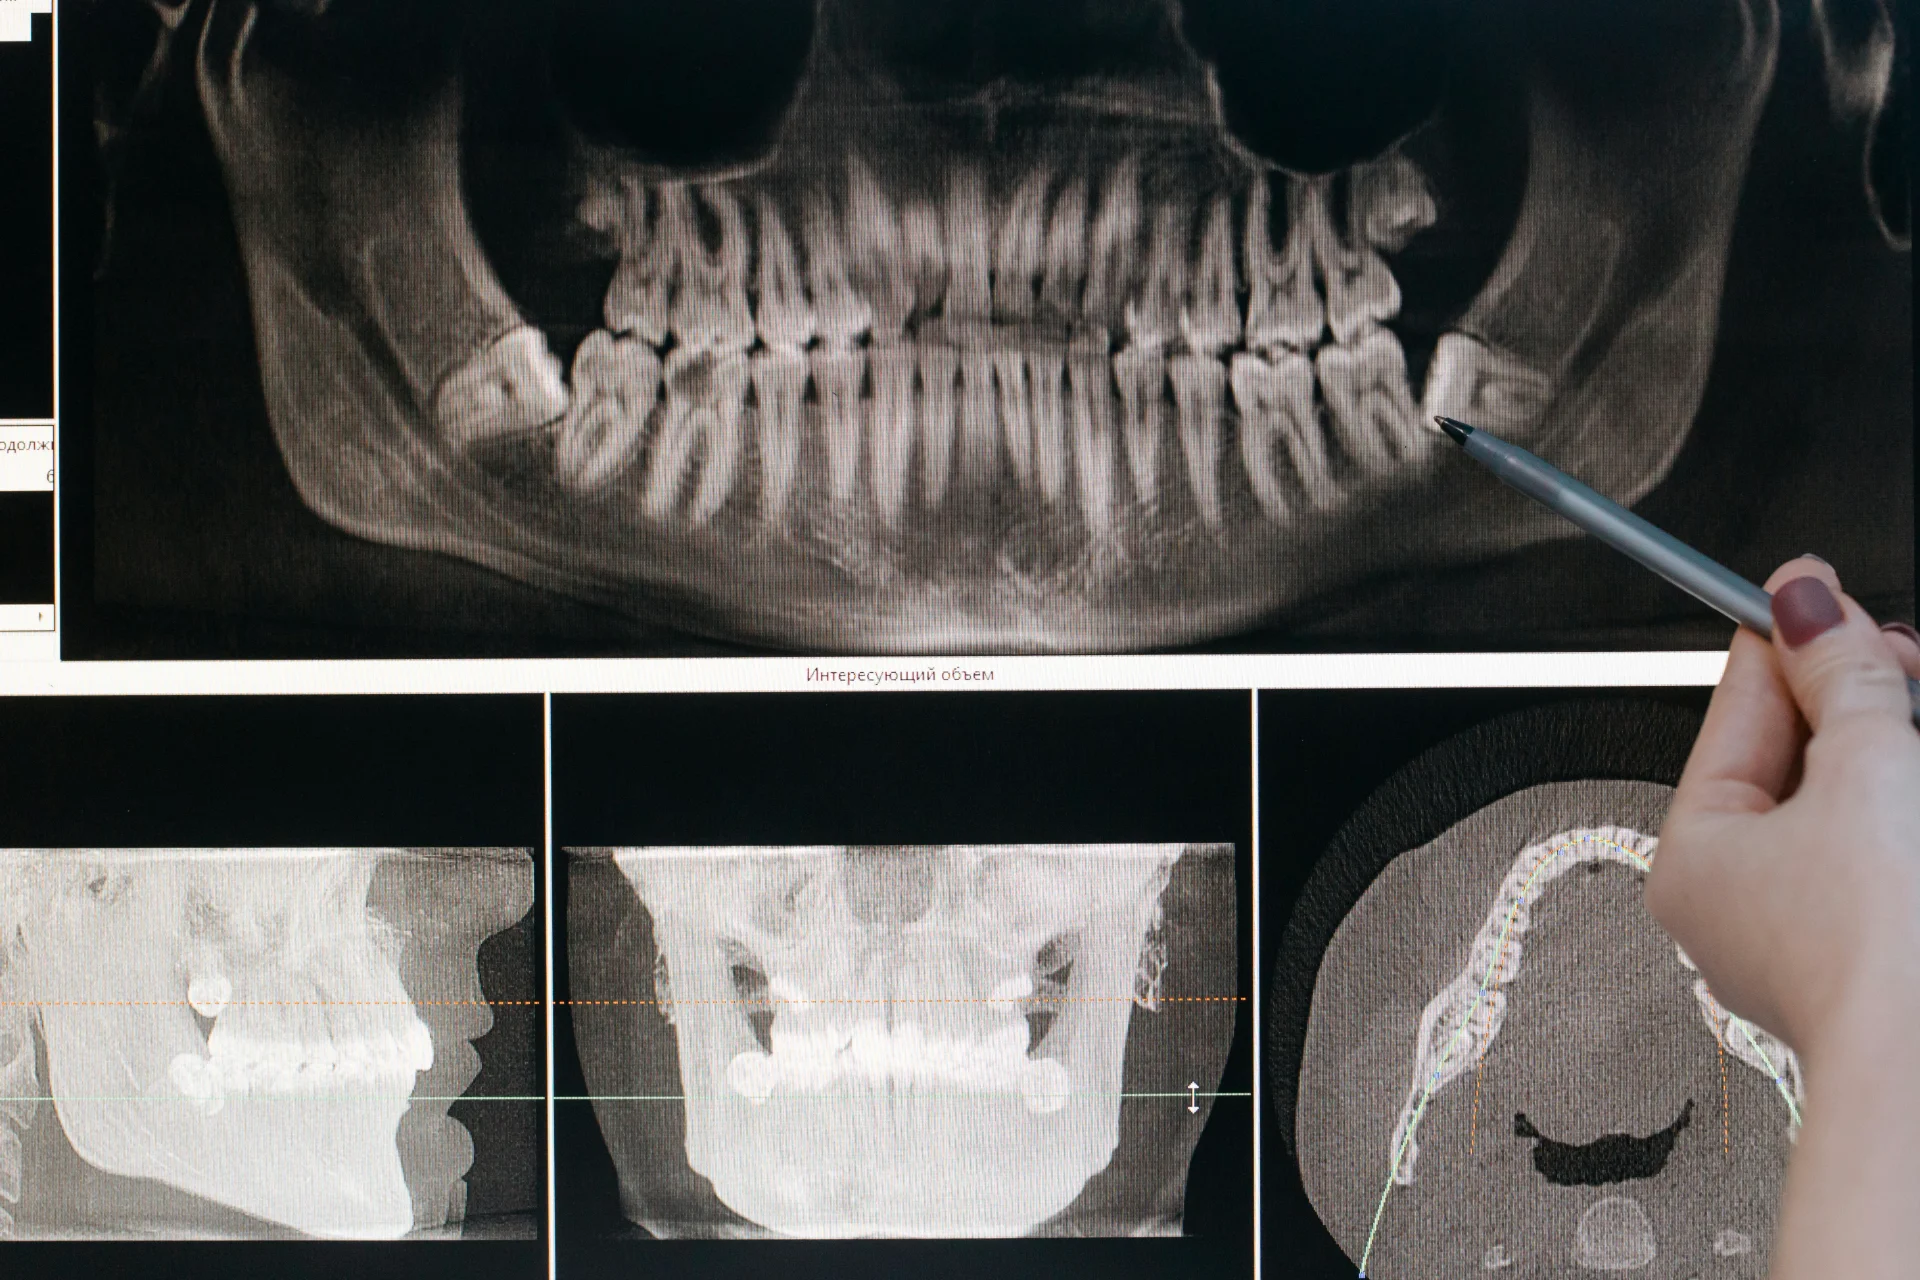

The scope of what an X-ray certification covers also varies. In the dental setting, it typically authorizes the holder to take standard intraoral radiographs (bitewings, periapicals, and occlusal images) as well as extraoral images such as panoramic radiographs. Some states have additional certifications or endorsements for advanced modalities like CBCT imaging. In the general medical setting, radiography certification covers a broader range of imaging procedures, though this guide focuses primarily on the dental pathway.